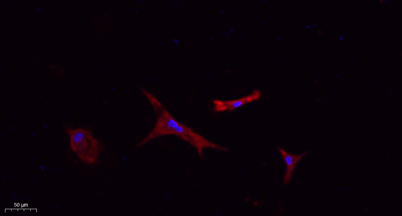

Flk-1/VEGFR2 rabbit pAb

Applications:WB;IHC;IF;ELISA